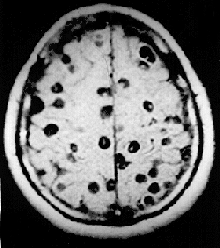

![]() Цистицерки в головном мозге. Магнитно-резонансное изображение. | |

Цистицеркоз головного мозга

Чаще всего (более 60 %) цистицерк попадает в головной мозг, реже в скелетные мышцы и глаза. Продолжительность жизни паразита в мозге от 5 до 30 лет. В большинстве случаев в головном мозге имеются сотни и тысячи паразитов, однако встречаются и единичные цистицерки. Они локализуются в мягких мозговых оболочках на основании мозга, в поверхностных отделах коры, в полости желудочков, где они могут свободно плавать. Погибая, паразит обызвествляется, однако, оставаясь в мозге, поддерживает хронический воспалительный процесс.

Диагностировать цистицеркоз головного мозга исключительно трудно из-за отсутствия патогномоничных симптомов. В постановке диагноза опираются на следующие особенности заболевания: множественность симптомов, указывающая на многоочаговое поражение мозга, преобладание явлений раздражения, наличие признаков повышения внутричерепного давления, смена тяжелого состояния больного периодами благополучия. Диагностике помогают рентгенографические данные, КТ, МРТ, а также эозинофилия крови и цереброспинальной жидкости, положительная РСК с цистицеркозным антигеном.